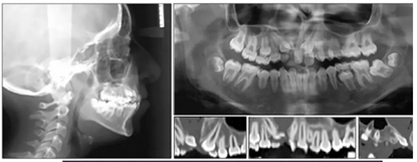

全景片示:側(cè)切牙扭轉(zhuǎn)、發(fā)育異常,影響上頜左側(cè)尖牙,下頜左側(cè)第二磨牙嚴重近中傾斜。幾乎所有的牙齒都是短根,但沒有觀察到牙根吸收的現(xiàn)象。

頭部側(cè)位片測量顯示骨性I類錯合畸形(ANB,3.5°),垂直生長模式(SN / GoMe,39°),上頜中切牙后傾(1 / SN,94°)和下頜中切牙前傾(IMPA,100 °)(圖3)。